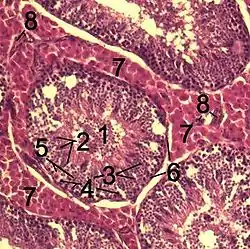

![]() Histological section through testicular parenchyma of a boar. 1. lumen of Tubulus seminiferus contortus 2. spermatids 3. spermatocytes 4. spermatogonia 5. Sertoli cell 6. myofibroblasts 7. Leydig cells 8. capillaries | |